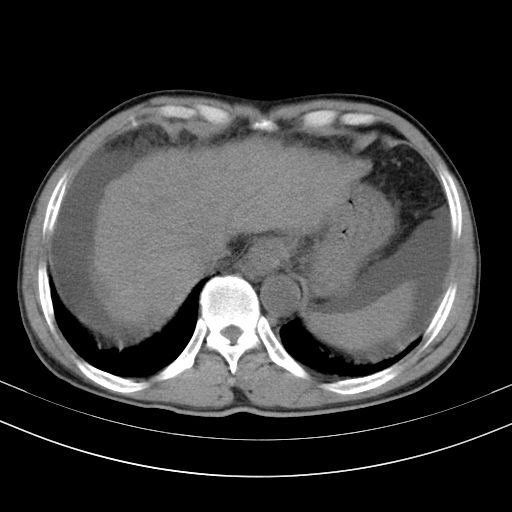

以下是引用随光逐影在2010-2-28 10:23:00的发言:[br]1)考虑肝癌;建议行ct增强扫描检查。2)肝硬化,脾大,腹水。3)慢性胆囊炎。